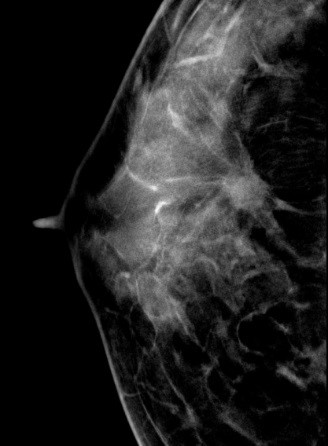

病史:患者43岁,发现右乳包块2周。

DBT图像:

常规2D图像MLO位上象限见一团块状影,在CC位上并没有发现可疑异常密度影,在V-Preview图像和tomo图像上我们可以清楚发现病变边界不清见长短不一毛刺,呈星芒样改变。

右乳上方略偏外局限致密影BI-RADS 4B 。

在TOMO图像上对星芒样病灶周边情况显示明显优于2D图像,最后病理证实右乳浸润性导管癌。